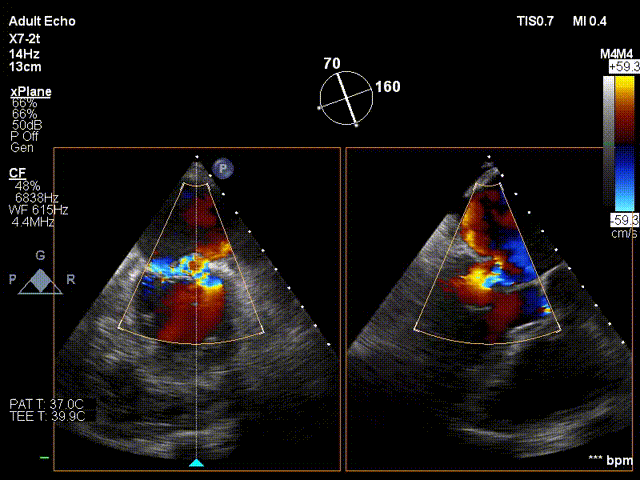

术前超声评估:

术前TTE超声提示二尖瓣大量反流